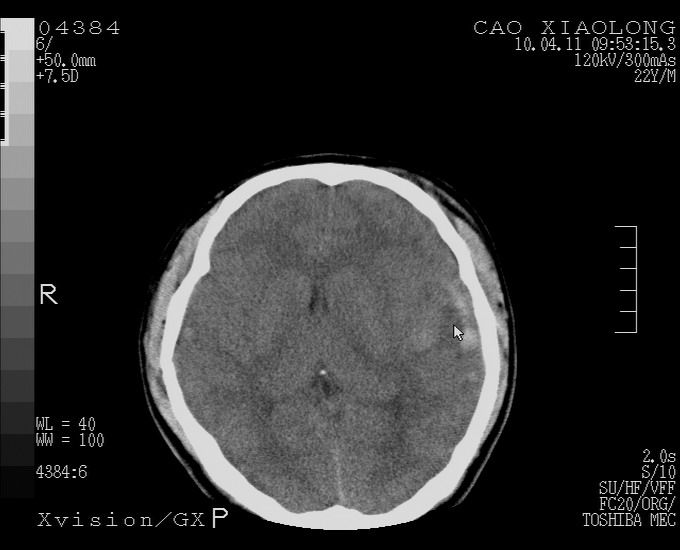

以下是引用随光逐影在2010-4-11 11:00:00的发言:[br]1)左侧额颞顶部硬膜下血肿。2)蛛网膜下腔出血。3)右侧颞顶部颅骨线形骨折。[br][br]20小时后复查:左侧额颞叶脑挫裂伤;左侧额颞顶部硬膜下血肿及蛛网膜下腔出血有吸收表现;右侧颞顶部颅骨线形骨折。[br]